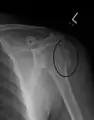

Fracture of the greater tuberosity of the humerus

Multi-fragmented, or comminuted fracture of the proximal humerus with involvement of the greater tuberosity